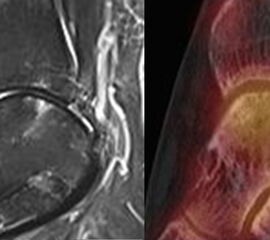

Abbildung 2.1.

Bildbeispiele symptomatische OCL

Zum Lesen der Bildbeschreibung und zur Vollansicht bitte das Bild anklicken. Bild: H. C. Rischke

Abbildung 2.2.

Bilder eines Patienten mit Z. n. mehrfachen Sprunggelenksdistorsionen in der Vergangenheit, besonders heftige Distorsion des linken Sprunggelenkes 5 Wochen vor der Untersuchung. Die SPECT/CT zeigt eine instabile osteochondrale Läsion mit deutlicher Aktivierung.